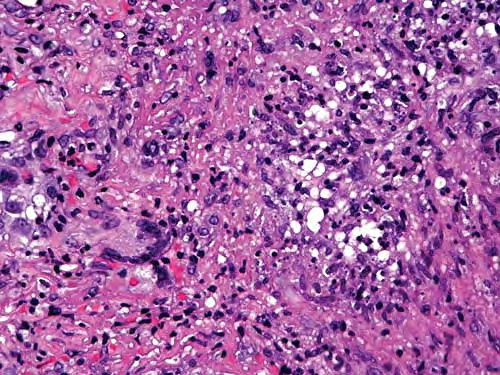

pathologic examination of tissue can reveal tuberculoid, palisading, and sarcoidlike granulomas; a diffuse infiltrate of histiocytic foamy cells; acute and chronic panniculitis; nonspecific chronic inflammation; cutaneous abscesses; suppurative granulomas; and necrotizing folliculitis. Suppurative granulomas are the most characteristic feature in skin biopsy specimens from cutaneous atypical mycobacteria infections. The evolution of the disease and the immunologic status of the host may explain this spectrum of morphologic changes.

Some authorities note severe inflammatory lesions involved with the dermis and the hypodermis; these can have 3 main histopathologic patterns: granulomatous nodular or diffuse inflammation with mixed granulomas, prevailing abscesses with mild granulomatous reaction, and deep dermal and subcutaneous granulomatous inflammation with no neutrophil component.